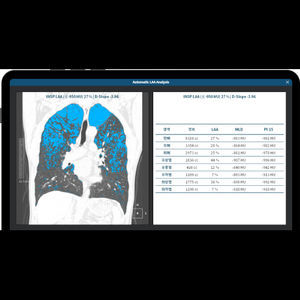

... torácicas. Solución automatizada de detección y análisis de nódulos pulmonares, EPOC y CAC aview LCS PLUS también puede utilizarse como tres productos individuales : EPOC, LCS y CAC Enfisema Análisis de enfisema Convierte ...

Coreline